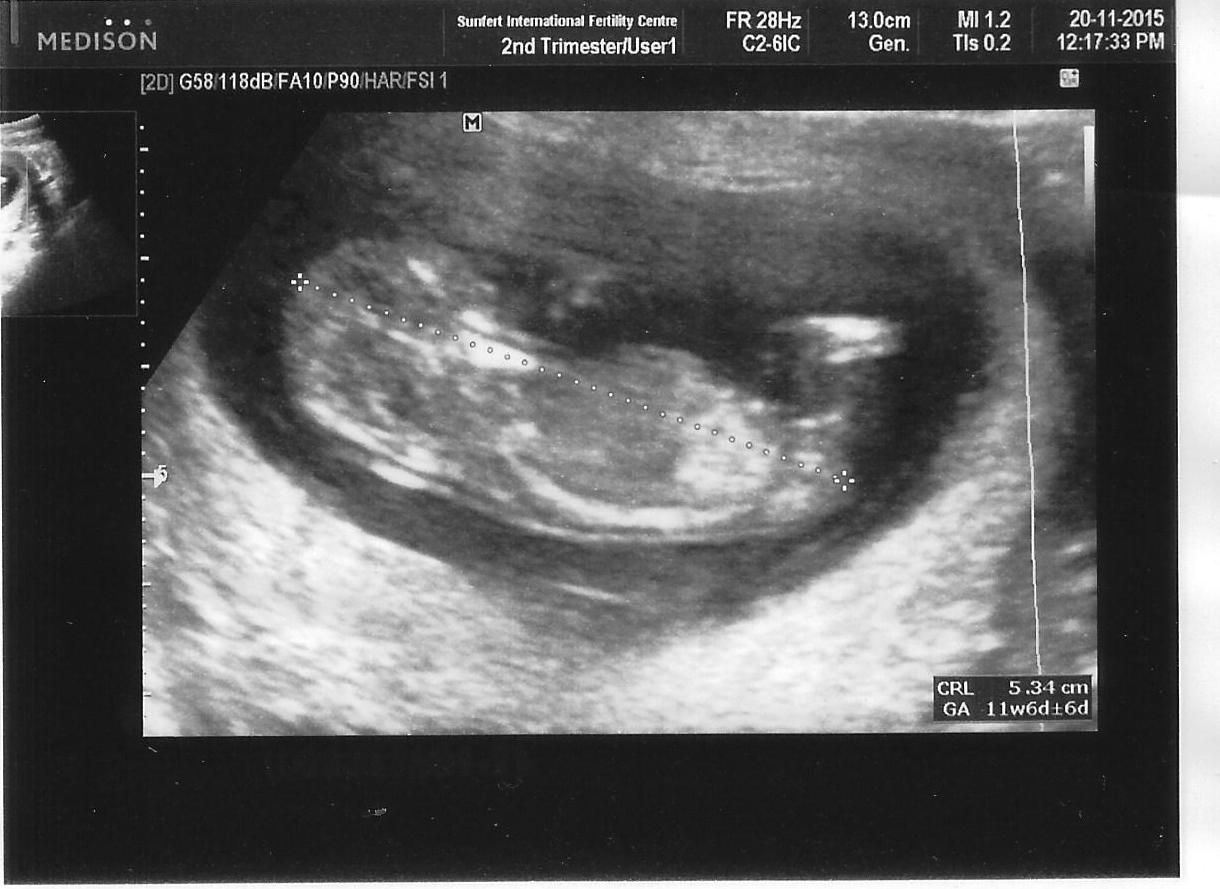

12 weeks ultrasound

Lil’ BB is now 12 weeks old. I didn’t expected anything when I see the ultrasound but when my gynae pointed out the head, Lil’ BB made a little leap! That was a pleasant surprise!

I can’t help but keep smiling as I see my Lil’ BB move about in the ultrasound. It was so amazing for me.

BB looks big in this picture but BB is only 5.34cm! Barely the size of my palm. And already so fully formed!